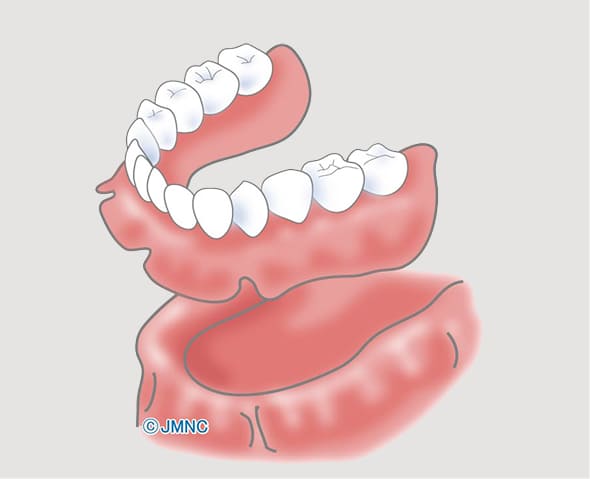

総入れ歯

入れ歯のバネを掛けていた歯もダメになり、そんなことを繰り替えすうちに、最終的には総入れ歯に…。